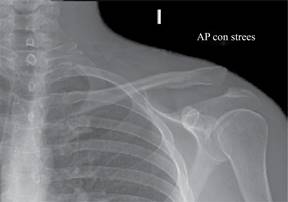

El objetivo de nuestra técnica quirúrgica es restaurar la estabilidad tanto vertical como horizontal de la articulación acromioclavicular (AC) mediante el uso de una técnica abierta de reconstrucción de la articulación AC con aloinjerto (semitendinoso o peroneus longus) para restaurar la estabilidad horizontal. Se realiza una reconstrucción anatómica de los ligamentos CC utilizando aloinjerto y fijación con dos tornillos de biotenodesis. En cuatro pacientes con diagnóstico de luxación AC grado III-V según la clasificación de Rockwood, clínicamente son pacientes con alta demanda funcional que presentaron un mecanismo de lesión de contusión directa con carga axial y brazo en aducción del hombro; posteriormente muestran deformidad en el tercio distal de la clavícula, con dolor en la articulación AC y limitación para la abducción del hombro y elevación del brazo. Mediante radiografías anteroposterior de hombro comparativas con carga y axial de hombro se hicieron los diagnósticos de luxación AC Rockwood III-V (Figura 1), por lo que se procede a realizar cirugía en etapa aguda.

Figura 1: Radiografía anteroposterior de hombro izquierdo con estrés. Se observa pérdida de congruencia articular acromioclavicular, con elevación hacia caudal de tercio distal de clavícula.